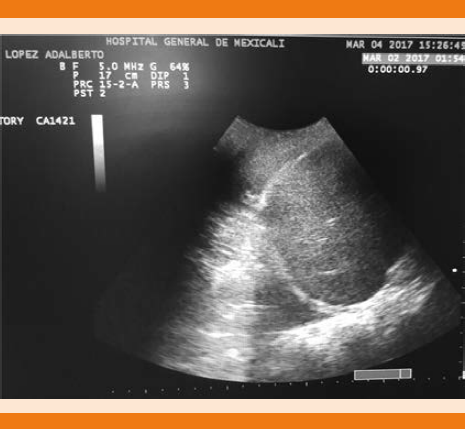

Figura 1 Radiografía de tórax anteroposterior en la que se observa borramiento del ángulo costofrénico y costodiafragmático. Derrame pleural.

La radiografía de tórax anteroposterior evidenció borramiento de ángulo costodiafragmático derecho e infiltrado basal (Figura 2), así como área de consolidación pulmonar (Figura 3).